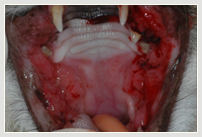

Die chronische Mundhöhlenentzündung (FC-GS Feline Chronic Gingivitis-Stomatitis, oder Plasmazellgingivitis) ist die zweite spezielle Katzenkrankheit.

Diese noch schmerzhaftere chronische Entzündung der gesamten Mundhöhle ist eine Erkrankung bei der die Katzen wegen der Schmerzen tatsächlich zu fressen aufhören. Diese eher selten vorkommende Erkrankung (0,5 – 1,5%) wird ebenfalls durch Bakterien und Viren gefördert. Weitere Ursachen sind geschwächte Immunität oder eine falsche Immunantwort der Katze. Die genaue Entstehung der Krankheit ist aber ebenfalls noch unklar. Festgestellt wurde lediglich eine vermehrte Infiltration mit sogenannten Plasmazellen, deswegen auch der Name Plasmazellgingivitis.

Meist ist auch hier die einzig wirksame Behandlung die Entfernung aller Zähne in der hinteren Mundhöhle. Zur Heilung auf Dauer muß die Katze bei dieser Erkrankung oft zusätzlich mit Antibiotika und Immunsuppressiva behandelt werden.